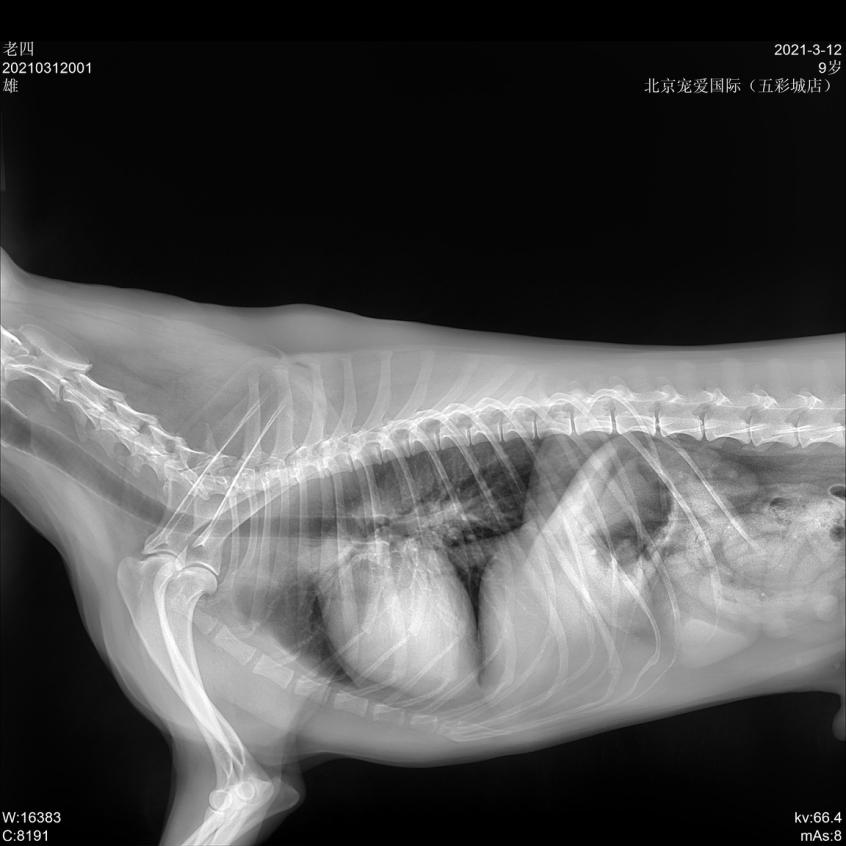

- 宠物名:老四

- 性别:男孩

- 年龄:8岁10个月

- 品种:喜乐蒂犬

- 体重:13.5KG

临床检查: TPR正常,精神沉郁,步态缓慢,肛门左侧有一大的鼓包,较软; 直肠检查肛周左侧有一疝孔。

x线检查

会阴疝